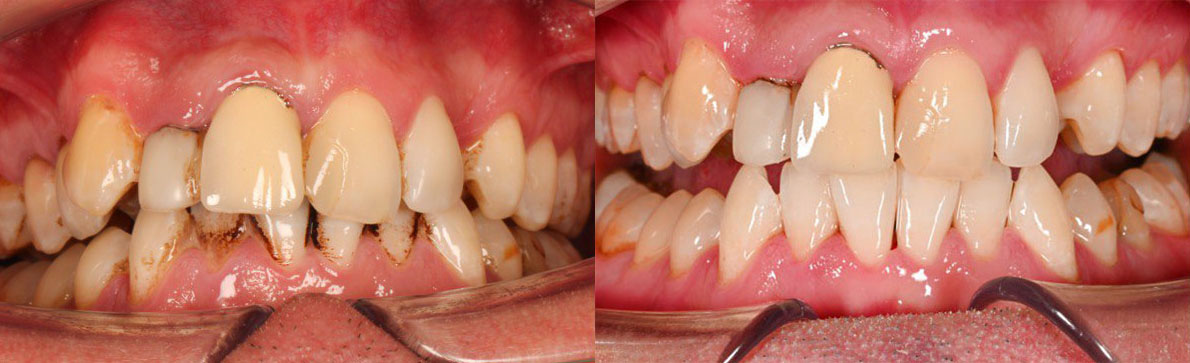

В ходе первичного осмотра выявлено значительное количество пигментированного налета и твердых зубных отложений, особенно в пришеечной области и на внутренней поверхности зубов. Также отмечались признаки воспаления десен, характерные для начальных проявлений гингивита. Пациенту были даны рекомендации по проведению комплексной профессиональной гигиены полости рта.

Пациенту проведена комплексная профессиональная гигиена полости рта. На первом этапе выполнено удаление твердых зубных отложений. Далее с использованием аппарата AirFlow произведено удаление пигментированного налета и мягких отложений с поверхности зубов. Завершающим этапом стала полировка эмали, направленная на создание гладкой поверхности и замедление повторного накопления налета.

После процедуры отмечено значительное улучшение цвета зубов и их внешнего вида. Поверхность эмали стала гладкой и чистой, уменьшились признаки воспаления десен. Пациент получил индивидуальные рекомендации по гигиене полости рта и поддерживающему уходу.